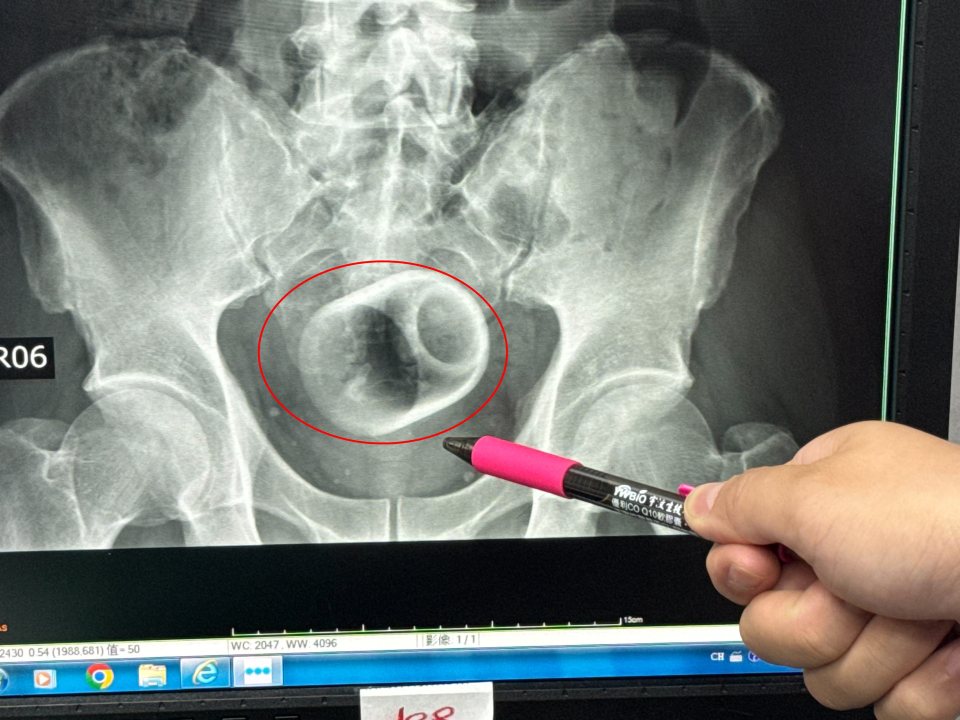

An X-ray revealed there was a ceramic cup inside him.

Measuring around 6cm wide and 8cm tall, medics tried to remove the piece of crockery.